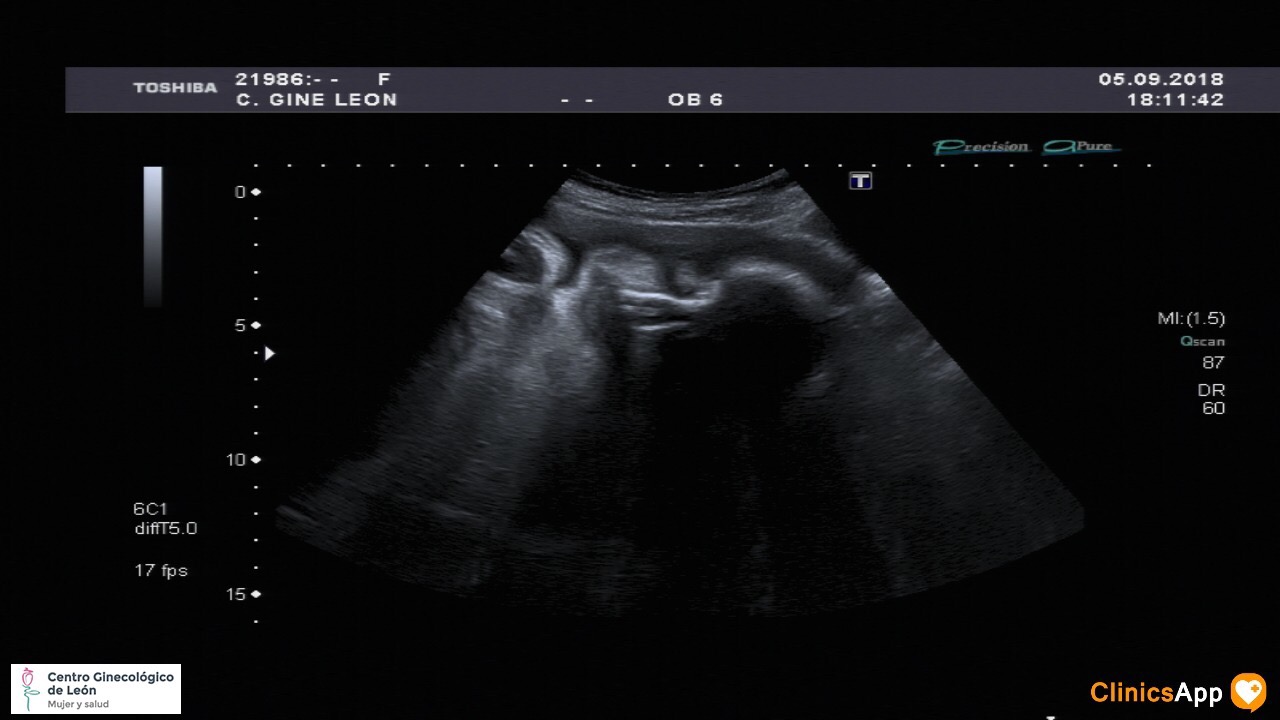

Nueva ecografía de la hermana de Mateo Nueva ecografía… y aún sin nombre. Ya pesa más de 2Kg, así que empieza a estar más apretada. Fecha publicación 05/09/2018 Publicada por papá Publicada en Fotos, Galerías, Prenatal Comentarios 0 Entrada anterior: Con mamá al parque Entrada siguiente: Caco balí n° 23 Deja una respuesta Cancelar la respuestaComentario * Nombre * Correo electrónico * Web Guarda mi nombre, correo electrónico y web en este navegador para la próxima vez que comente. Recibir un correo electrónico con los siguientes comentarios a esta entrada. Δ